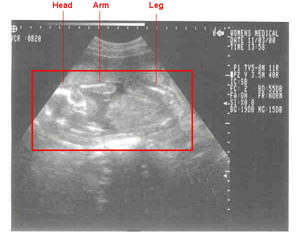

11/03/2000--Head-on shots at 20 weeks. Weight approx. 1 pound.